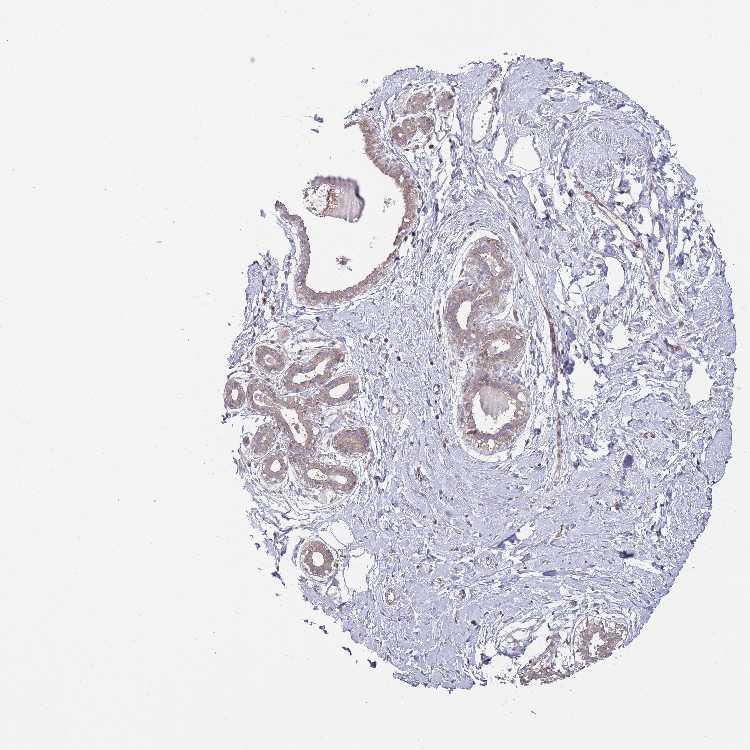

BREAST - Antibody stainingi

Antibody staining in the annotated cell types in the current human tissue is reported as not detected, low, medium, or high, based on conventional immunohistochemistry profiling in selected tissues. This score is based on the combination of the staining intensity and fraction of stained cells.

Each image is clickable and will lead to virtual microscopy that enables deeper exploration of all samples and also displays staining intensity scores, fraction scores and subcellular localization as well as patient and tissue information for each sample.

Antibody HPA049926Antibody HPA053406

Adipocytes Not detectedNot detected

Glandular cells MediumMedium

Myoepithelial cells MediumNot detected